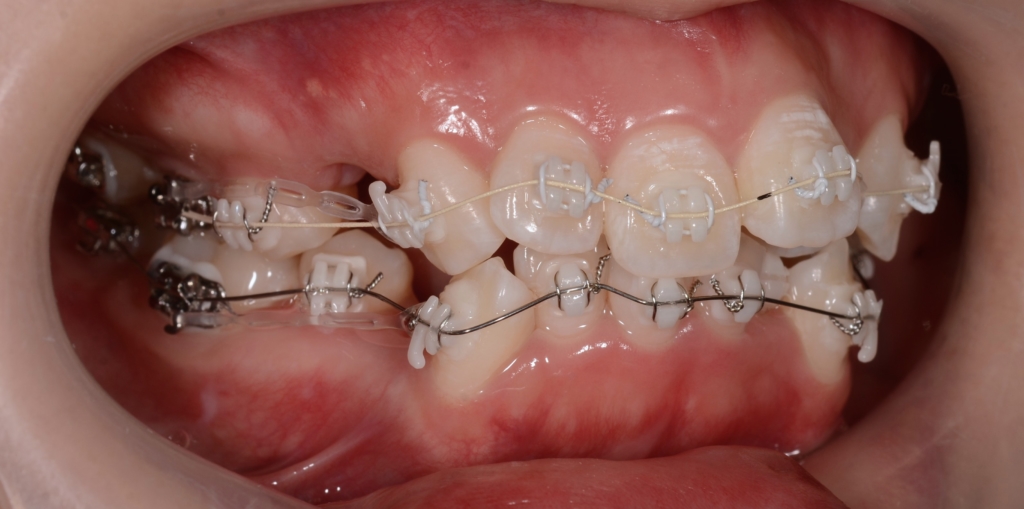

【治療装置】

マルチブラケットシステム(ハーフホワイトtype)で矯正治療を開始。

前歯の乱れが解消され、きれいに並んだので、次のステップに入ります。

上下とも前歯を後方へ最大限に引っ込めて行きます

この方の写真が見つからないので、同じことをしている方の写真をイメージ写真としてあげています

【途中経過】 当初に抜歯をして出来たスペース分は、しっかりと引っ込めることが出来ました。

ただ、元の噛み合わせが出っ歯だったので、「出っ歯」が残ってしまいました。

そこで、アンカースクリューを追加して更に引っ込めることにしました。

上顎の口蓋の中央部に2本植立しました。

上顎のアンカースクリューにはPLAS & 奥歯の内側にはパラタルバーを付けて、上の歯列(歯並び全体)を出来るだけ後方へ引っ込めて行く「矯正力」を加えて、治療を再開しました。